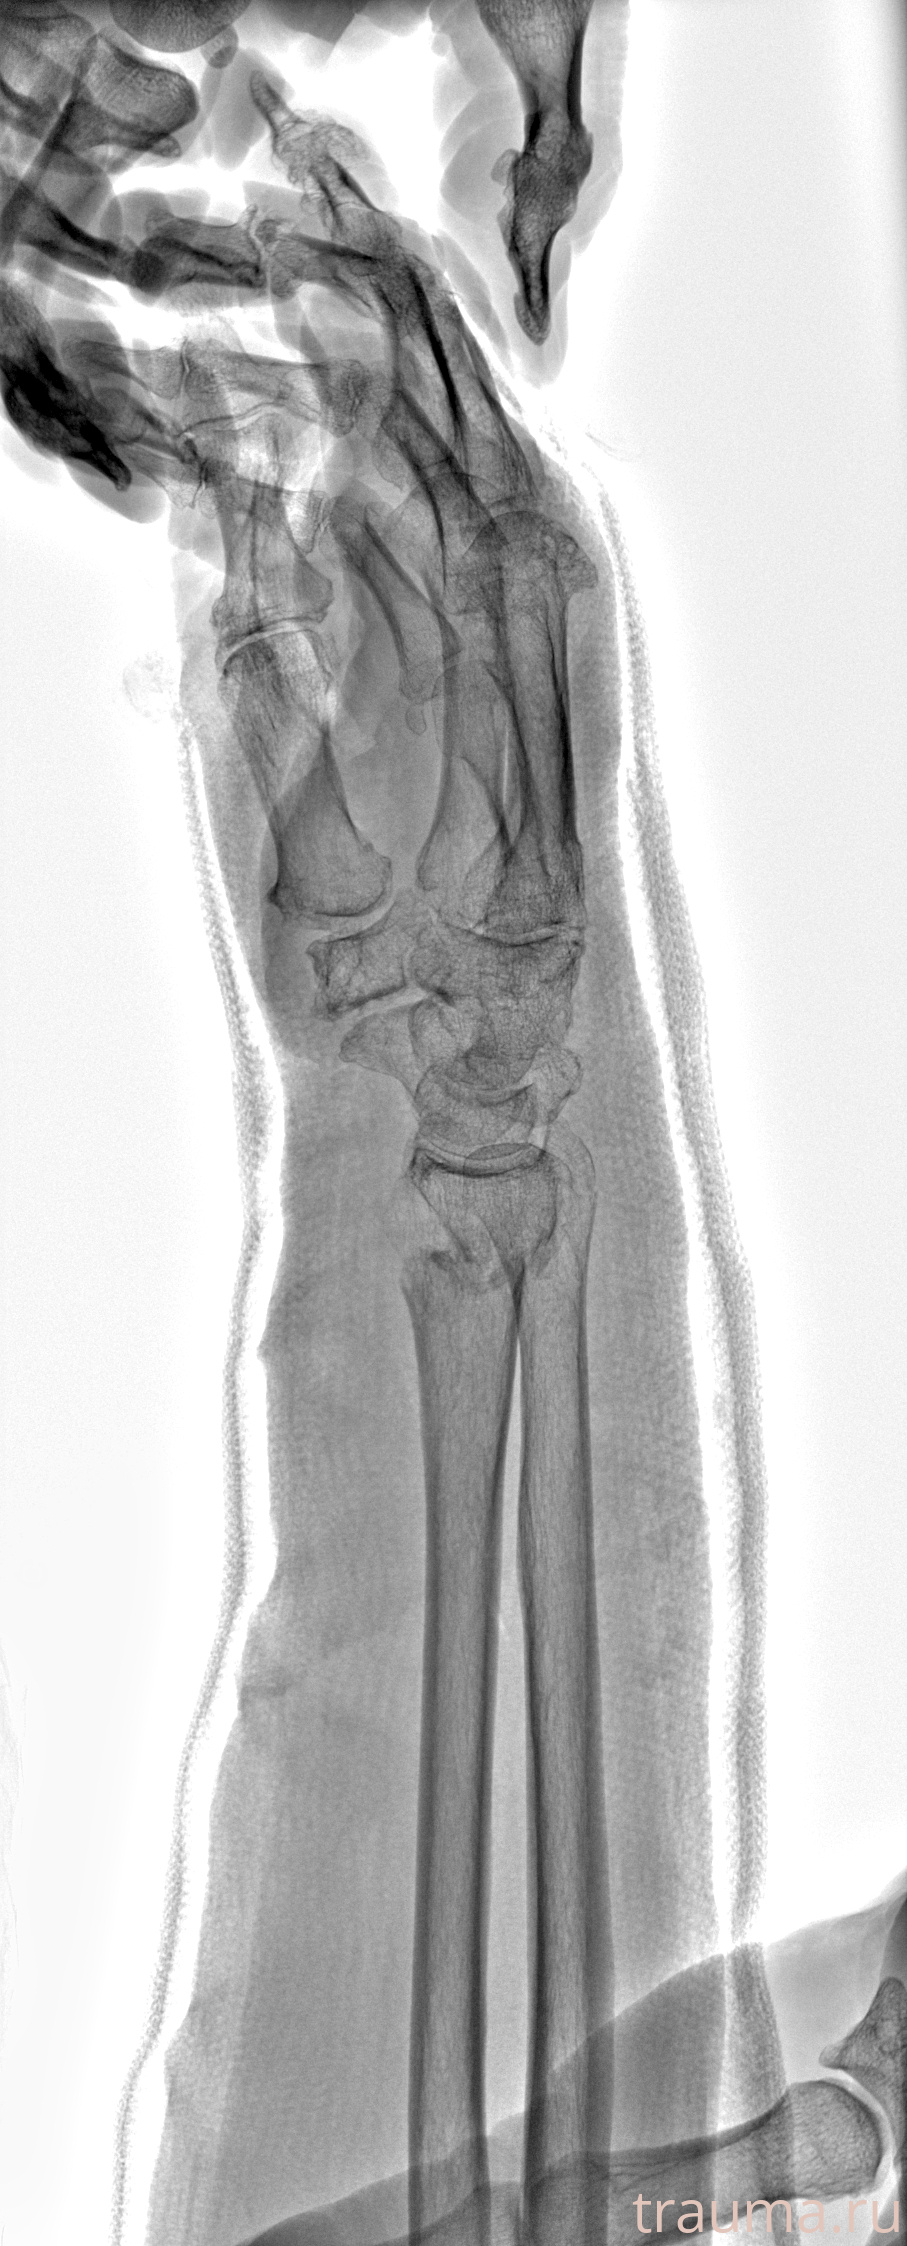

Рентгенограммы

Рентген на дому: по вашему адресу приезжает врач-рентгенолог, травматолог-ортопед с мобильным рентгеновским аппаратом, проводит диагностику травмы или заболевания, делает необходимые рентгенограммы, дает рекомендации по дальнейшему лечению. Получить качественные снимки в домашних условиях возможно благодаря уникальной методике, разработанной МосРентген Центром для института  Склифосовского